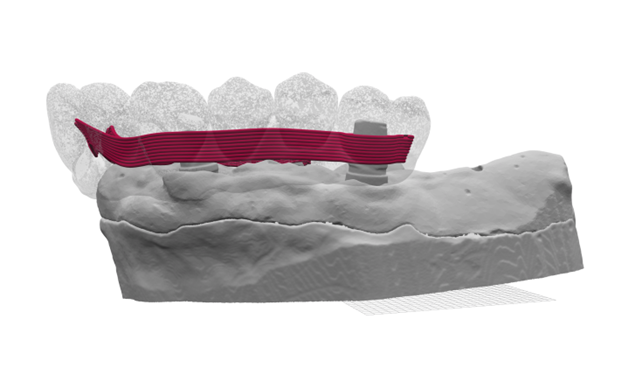

Fig. 17 Visualizzazione digitale laterale della barra Hi-Fiber

Il processo è stato molto agile: il laboratorio ha creato i volumi, e i file sono